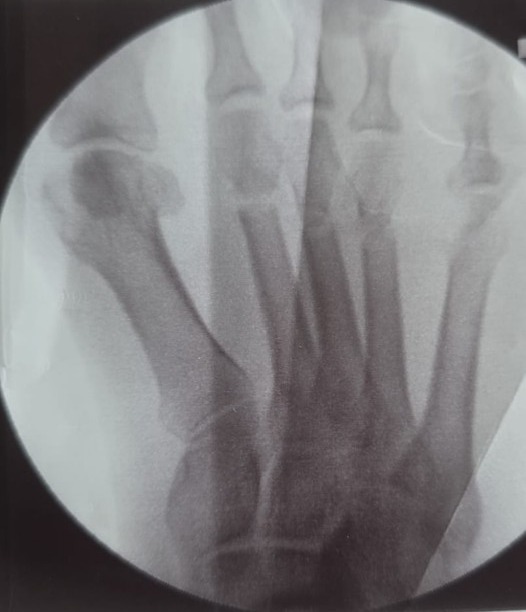

Home Schwerpunkte Krankheitsbilder Sichelfuß (Pes adductus): die häufigste angeborene Fußfehlstellung — und warum sie beim Erwachsenen oft unerkannt bleibt sichfeluss und tmt 1 vor korrektur sichfeluss und tmt 1 vor korrektur Sichelfuß Hallux Valgus Korrektur mit TMT 1 Arthrodese und DMMO 2 4 vor Korrektur